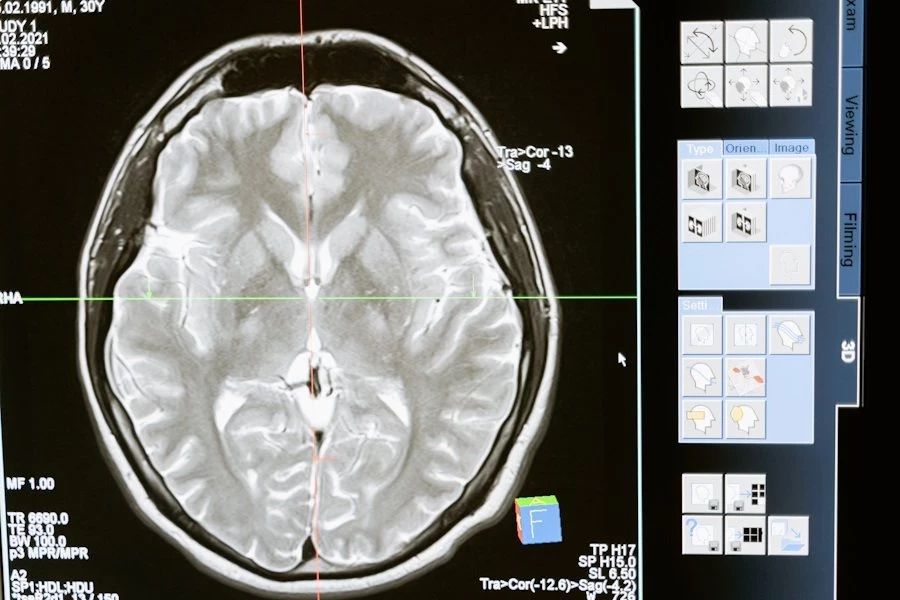

Nature: глиоцидин - новое оружие в борьбе с раком мозга

Ученые из Memorial Sloan Kettering Cancer Center (США) добились значительного прорыва в лечении глиобластомы — одной из самых агрессивных форм рака мозга. Ими была идентифицирована молекула глиоцидин, способная избирательно уничтожать клетки глиобластомы, не повреждая при этом здоровые ткани организма, сообщает Nature.